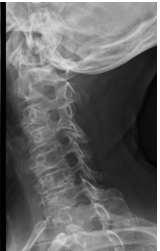

Incidências radiográficas de coluna cervical

2. Perfil:

A

Aparecem as vértebras até C7 (coluna cervical)

12

Q

Lesão degenerativa discal

aonde estão as lesões nas imagens?

1. Lesão degenerativa discal de C5-C6- C7

2. Lesão degenerativa discal de L2-L3-L4-L5